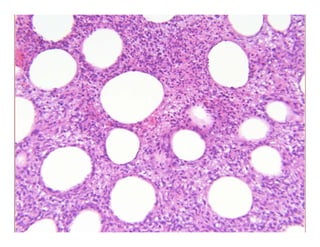

ParaffinomaParaffinoma

k S l i li lk S l i li laka…Sclerosing lipogranulomaaka…Sclerosing lipogranuloma

Special form of facticial panniculitis resulting from injection of lipiSpecial form of facticial panniculitis resulting from injection of lipi

(often paraffin) into subcutaneous tissue(often paraffin) into subcutaneous tissue

Well circumscribed noduleWell circumscribed nodulee c cu sc bed odu ee c cu sc bed odu e

? Swiss cheese appearance? Swiss cheese appearance

Bands of hyaline fibrous tissue between fat cells and cystic spacesBands of hyaline fibrous tissue between fat cells and cystic spaces

ParaffinomaParaffinoma k S li li lk S l i li laka…Sclerosing lipogranulomaaka…Sclerosing lipogranuloma Special form of facticial panniculitis resulting from injection of lipiSpecial form of facticial panniculitis resulting from injection of lipi (often paraffin) into subcutaneous tissue(often paraffin) into subcutaneous tissue Well circumscribed noduleWell circumscribed nodulee c cu sc bed odu ee c cu sc bed odu e ? Swiss cheese appearance? Swiss cheese appearance Bands of hyaline fibrous tissue between fat cells and cystic spacesBands of hyaline fibrous tissue between fat cells and cystic spaces